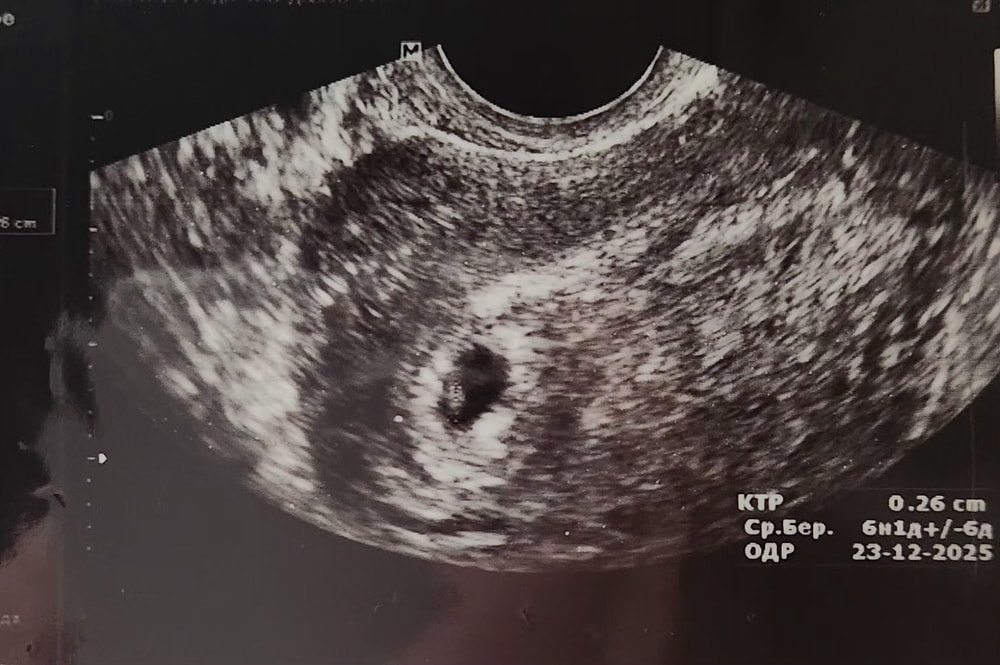

Сходила на УЗИ - все в порядке, растем) сб не получилось поймать, но пульсация видна на мониторе.

Про кровомазание - сказала, что все ещё прикрепление. И правда, пя слезло с верхушки матки пониже и правее, от этих перемещений и кровило.